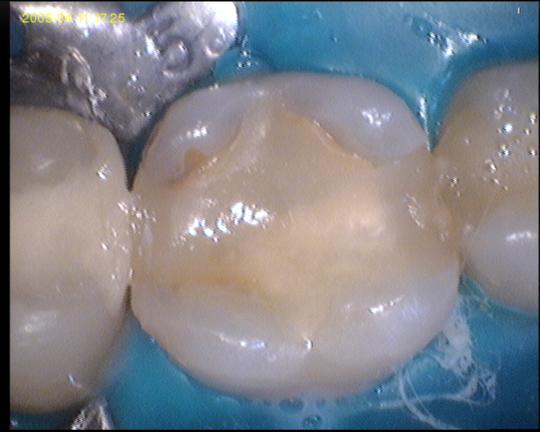

Tooth colored composite gradia, or white fillings seemed like a perfect solution at the time. It has no metals in it at all, and definitely no mercury, instead, it is entirely made up of artificial resin. This resin is made of modified plastics of course, but so is everything else, and so the impact on the environment is not particularly heavy. However, there is a slight problem. The material leaches BPA over time, and the longer you have the fillings, he more BPA will be leached into your system, which is not good for it.